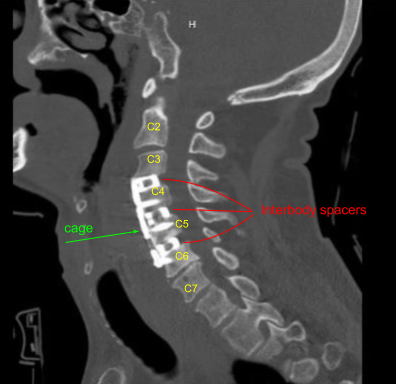

Bilateral foraminotomies were done using Kerrison punch 3.0. All the discs were thoroughly decorticated to achieve fusion. Once adequate foraminotomy and discectomy was done, a spacer was inserted to size the disc. After sizing, 8-mm Globus titanium cage filled with titanium interbody spacer, filled with autologous bone graft, mixed with Trinity and DBX was inserted finding it in adequate position.

Attention was moved to the C4-5 disc space. Caspar pin was inserted into the C5 body and expansion of C4-5 done with a self-retaining retractor. Skyline was moved inferiorly to retract medially and laterally. Discectomy was done in a similar fashion followed by excision of the posterior longitudinal ligament and bilateral foraminotomies. After adequate excision the sizing was done, Globus titanium spacer filled with Trinity and autologous bone graft and DBX was inserted again.

Again, a new pin was inserted into the C6 body and similar discectomy was done using curettes,matchstick bur and Kerrison punches. PLL was also excised. Bilateral foraminotomies of C5-6 was performed. A matchstick bur was used each time to make holes into the end plates for better fusion.

The cage was inserted, again packed with autologous bone graft, Trinity and DBX. After inserting all the three cages, the bony contouring was done using matchstick bur and plate was put of an adequate size. The plate was found to be adequate in AP and lateral views in a satisfactory position.

The plate was fixed using locking variable angle screws in the body of C3, C4, C5, and C6. Final pictures were taken and saved. The wound was thoroughly washed and hemostasis was achieved. The retractors were removed. Closure was done in layers using #2-0 Vicryl and Monocryl. Dressing was applied.